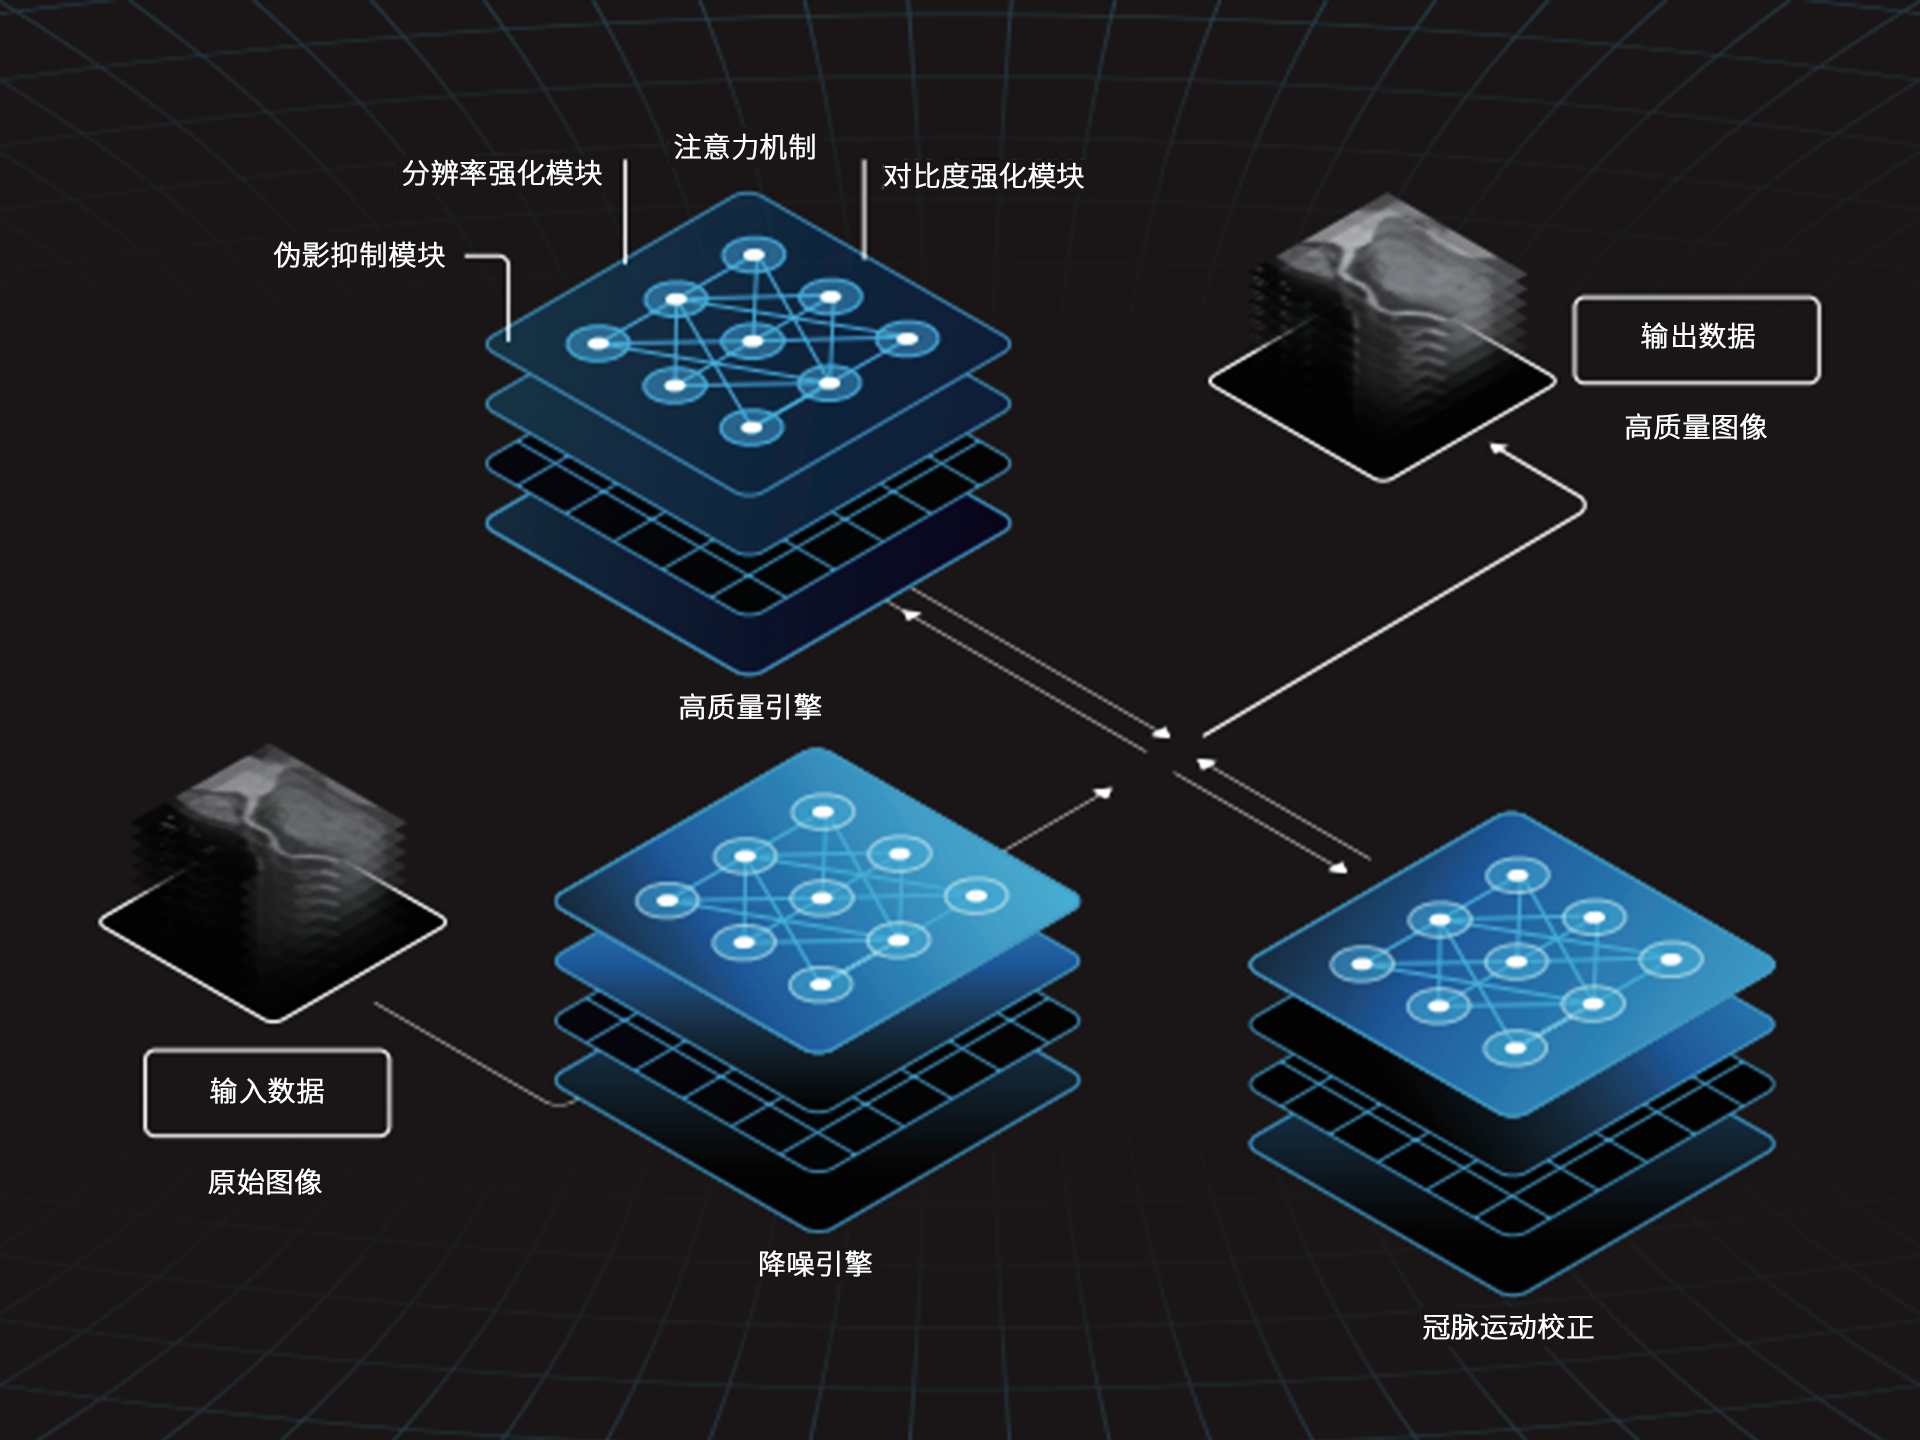

CardioBoost:专属网络设计,重塑心脏影像表现

相同辐射剂量下

低对比度分辨率提升

相同辐射剂量下

空间分辨率提升

相同低对比度分辨率下

辐射剂量减少

相同辐射剂量条件下

图像噪声减少